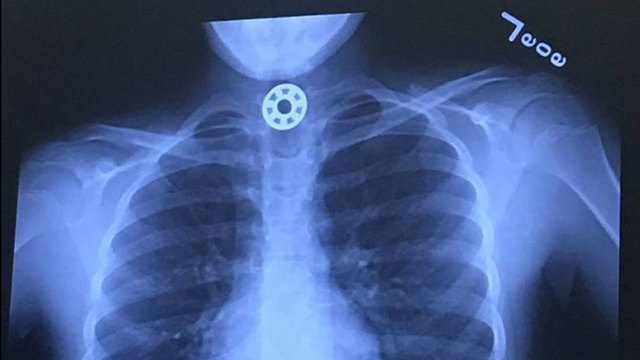

in Texas a mom says her 10 year old daughter nearly choked to death when one of the metal bushings from the spinner got lodged in her throat the girl claimed she was cleaning the spinner when the piece fell off